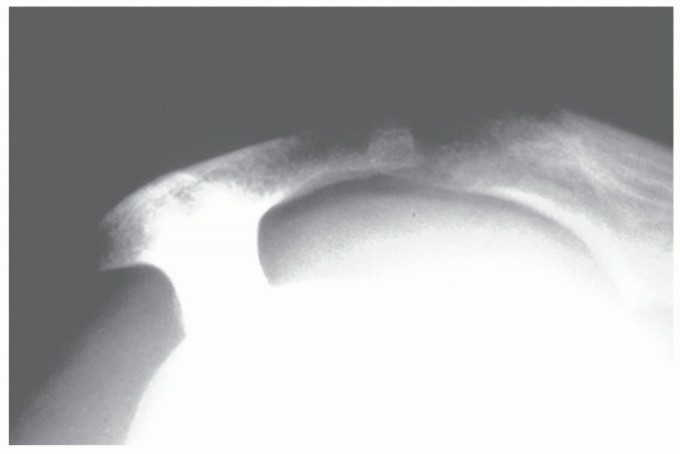

FIG 1 • A,B. Type III acromion, the so-called hooked acromion, on the outlet and AP views. C. Arthrogram confirming the presence of a rotator cuff tear with dye in the glenohumeral joint and the subacromial bursa simultaneously. D. T2-weighted coronal MRI showing cuff tear and its lateral to medial extent. E. T2-weighted sagittal oblique MRI showing the AP extent of the cuff defect. F. Another T2 sagittal oblique MRI showing the tear involving the teres minor but not the subscapularis. G. Axial T2 MRI of the same tear showing rupture of the teres minor with an intact subscapularis.

Standard radiographs, including anteroposterior (AP) views in internal and external rotation, an axillary view,

and an outlet view, should always be taken to look for the type of acromion (

FIG 1A

), acromioclavicular joint changes, and narrowing of the acromial-humeral interval (

FIG 1B

) and to rule out other conditions.